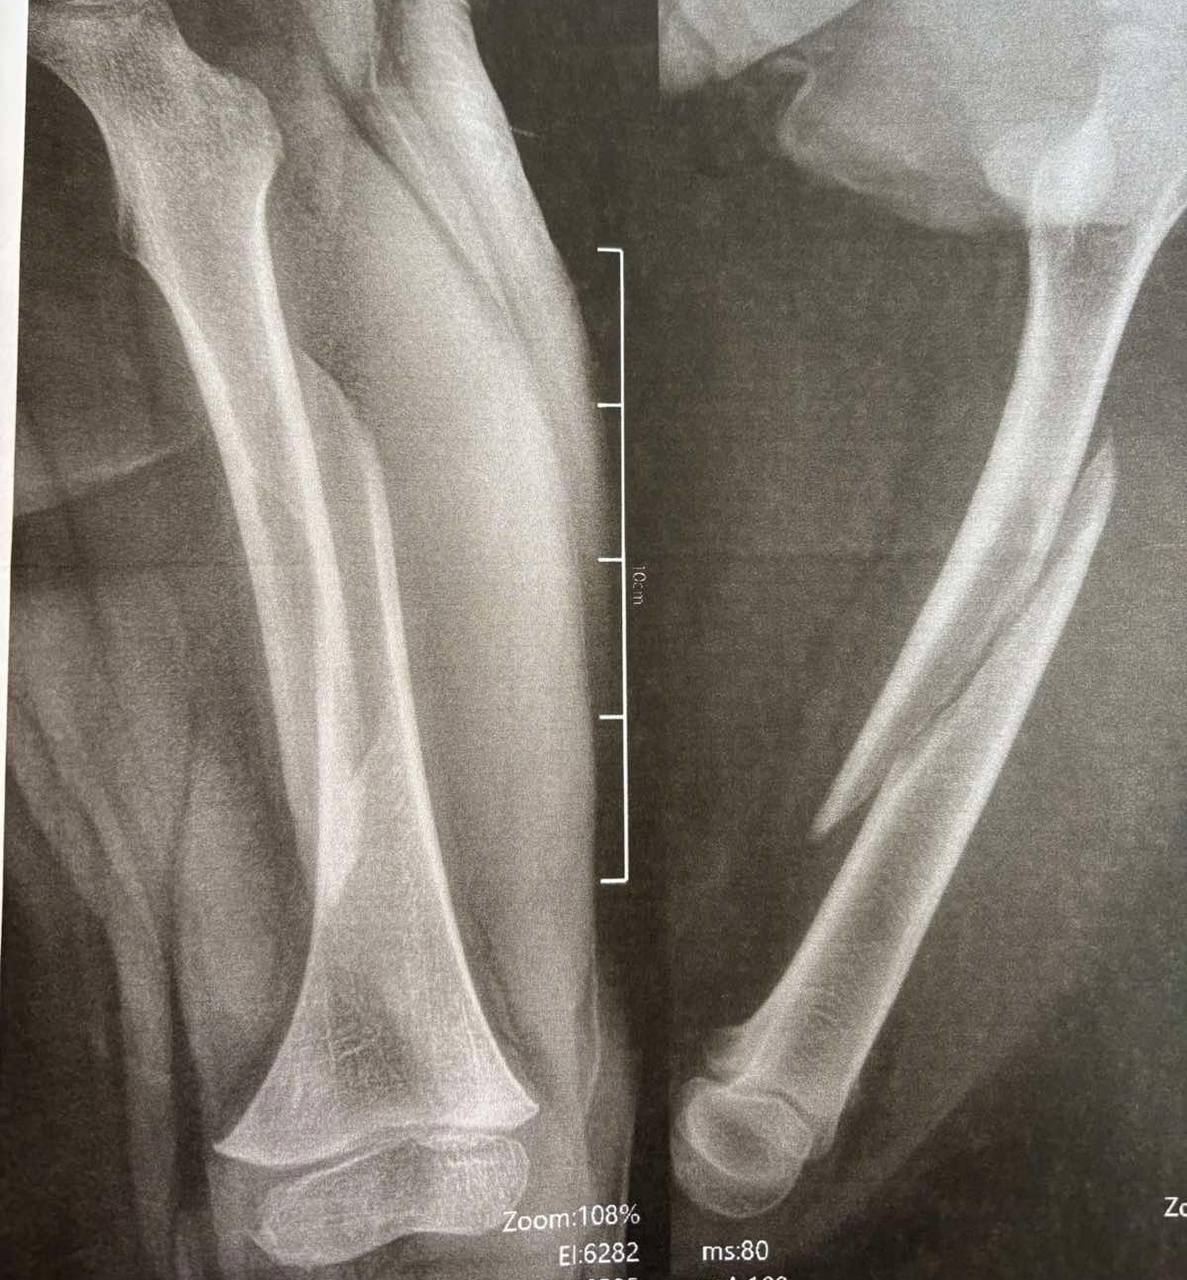

Дворічний Даніель отримав важку травму вдома – бігав, упав. Як наслідок – косий перелом стегнової кістки, складний для вправлення та лікування, утримання відламків.Ортопед-траматолог Ігор Тарасюк пояснює: «Лікування гіпсовими пов’язками хлопчику не підходить, тож раніше діти з такими травмами лікувалися впродовж місяця на витяжінні, а після цього застосовували кокситну гіпсову пов’язку, яка утруднювала рухи. Завдяки внутрішньокістковій фіксації еластичними титановими стержнями дитину виписуємо додому вже наступного дня. Хлопчик, хоч і з певними обмеженнями, але вже може самостійно рухатися».Ще одна пацієнтка відділення — 11-річна футболістка Юля, яка невдало впала на плече під час гри. Як наслідок – перелом плечової кістки зі зміщенням. Раніше через такий перелом довелося б носити велику гіпсову пов’язку на руці – від кисті до плеча, також гіпс накладали б для фіксації і на обидва плеча.Після операції через два-три дні дівчинка вже вільно рухає рукою, не відчуває обмежень. На руці залишиться лише невеликий шрам у 2-3 сантиметри. Через кілька тижнів дівчинка зможе повернутися до занять футболом.Читати ще: Арахіс у легенях, магніти в стравоході та опіки від побутової хімії: волинські лікарі розповіли, із чим до них привозять маленьких пацієнтів